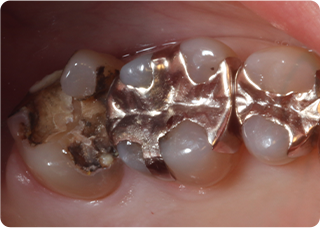

精密根管治療④

術前

術後

| 主訴 | 奥歯で噛むと痛い |

| 治療期間/回数 | 1ヵ月、3回 |

| 価格(税込) | 88,000円(税込) |

| リスク・副作用 | 病変再発、歯根破折の可能性 |

| ポイント | う蝕検知液を用い、むし歯の取り残しが無いようにし、ラバーダム防湿を行い、無菌的に根管治療を行った。根管充填材は、殺菌作用の強い保険適応外のMTAセメントを使用した。 |